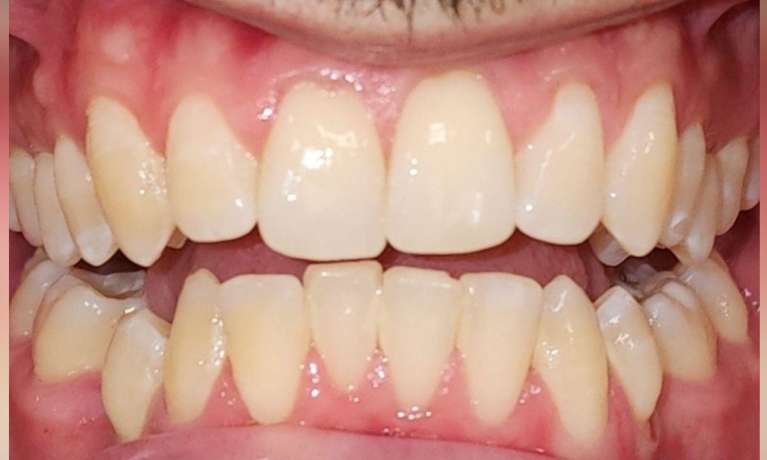

This patient came to us with some front teeth crowding, which was fixed with an Invisalign treatment. This gradually aligned the teeth leading to a straighter and more harmonious smile.